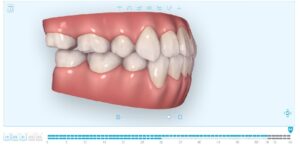

以下にコンピュータシュミレーションの最終予想を示します。

【治療終了シュミレーション】

このように、当院ではマウスピース矯正にてここまでの治療が可能です。